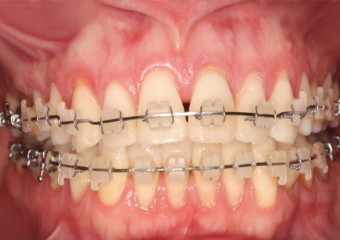

Sorriso Inicial